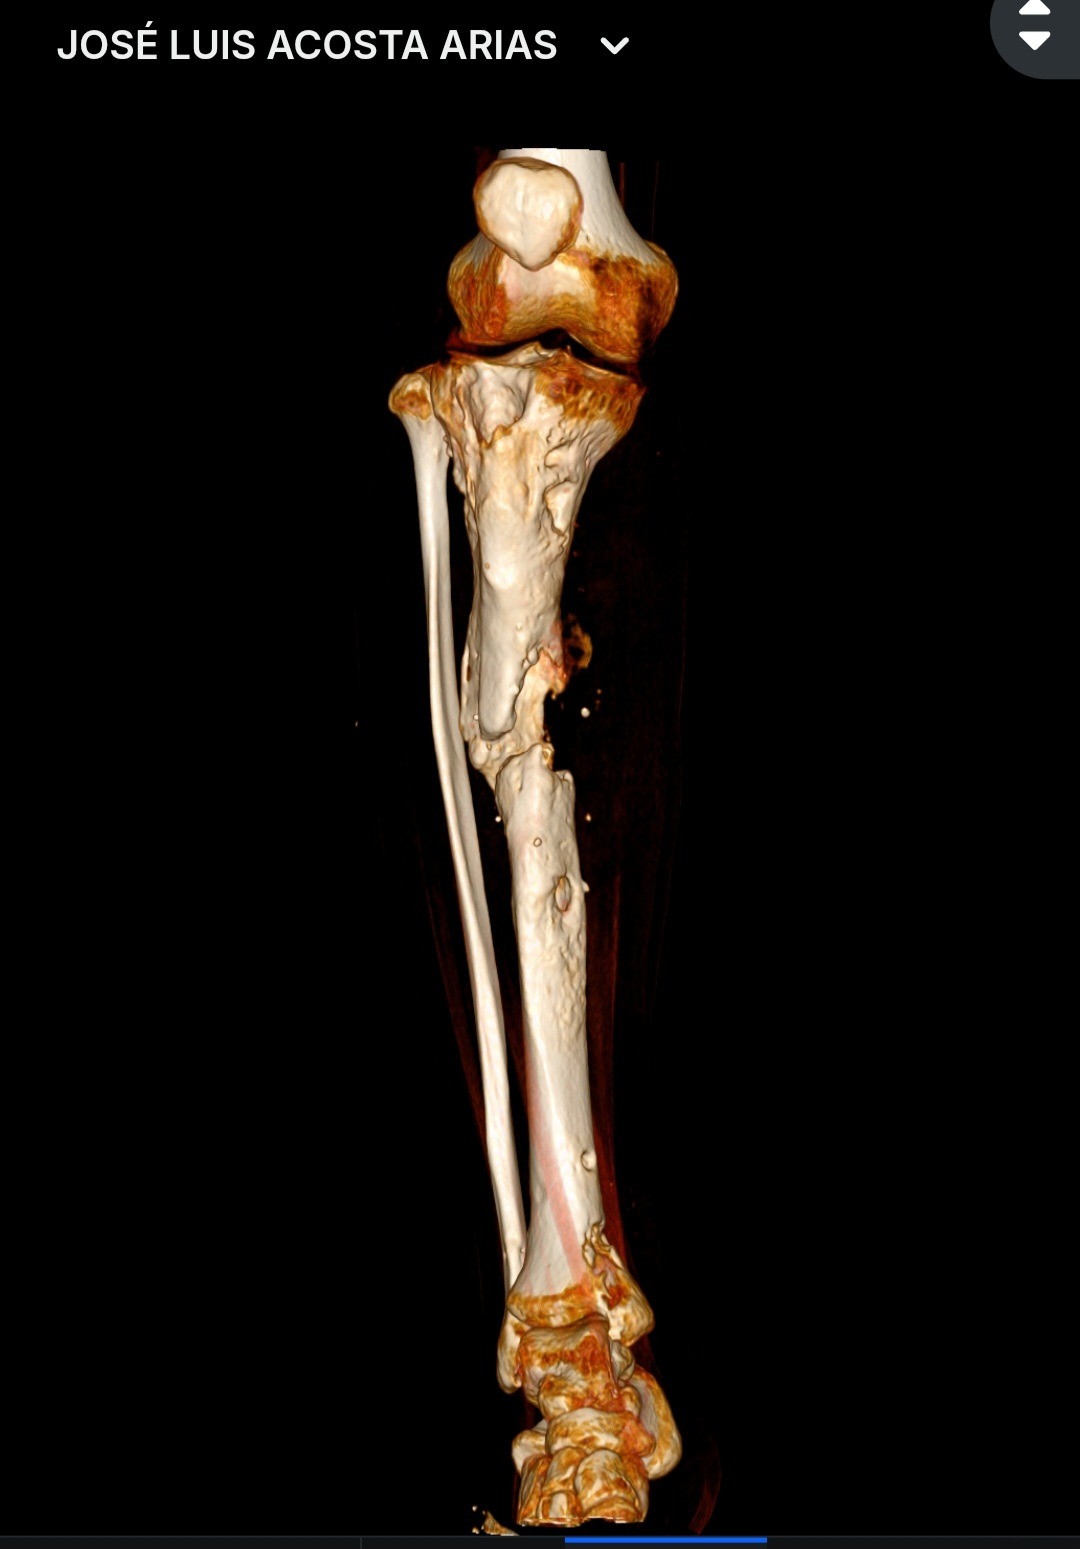

Hace más de un año y medio debido a un accidente practicando cheerleading me rompí la pierna. Todo iba muy bien hasta que comencé con un rechazo de material. He pasado por 3 cirugías para poder volver a caminar pero las cosas se conolicaron... tengo ya una infección en el hueso (osteomielitis) hace poco me dijeron que estaba apunto de perderla por ello (Las imagenes son de mi Xray y mi tomografía). Antes sentía que volaba, y ahora estoy anclado a una cama.

La cirugía consiste en los siguientes pasos:

•Realizar un lavado quirúrgico y recolección de cultivos de la bacteria que está en el hueso y saber cual es la que está afectando.

•Realizad un segundo lavado quirúrgico y colocar perlas con el antibiótico que puede atacar la o las baterías que se encuentre.

•Cortar la parte del hueso infectado (me dice el ortopedista que un hueso con osteomielitis ya no puede pegar nunca).

•Ver evolución del hueso con el antibiótico.

•Colocar un injerto en el espacio del hueso retirado y colocar un clavo intramedular para tener soporte.

Cómo pueden ver es un procedimiento largo, agresivo pero me comentaron que tiene altas probabilidades de resultados muy favorables.